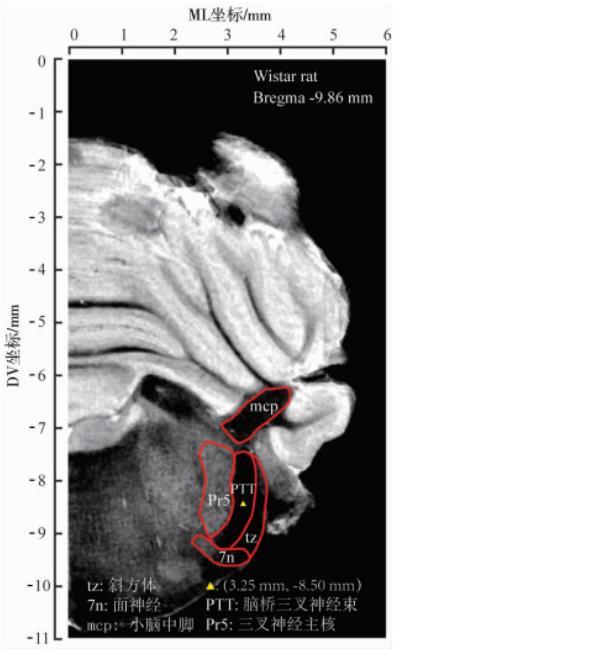

大鼠腦橋三叉神經束ML范圍較窄(約0.5 mm),背腹徑(dorsal-ventral,DV)范圍相對寬厚(約1.8 mm),且在冠狀面上呈傾斜弧形(圖1),使得垂直型腦立體定位精準微量注射難度較大,故本研究擬進行傾斜型腦立體定位微量注射,以增加微量注射容錯率和成功率。動物準備如前所述,在AP-9.86 mm和ML 0 mm處的顱骨表面鉆1個小孔,使玻璃微電極左傾斜18°進針9.22 mm,停留1 min后以250 nL/min的速度注射20 nL藍墨水或者相應劑量的LPC或Vehicle,注射完成后留針5 min,緩慢升起電極。縫合頭皮創口并消毒,取下動物待其恢復清醒后放回飼養籠。

圖1 Wistar大鼠腦橋三叉神經束MRI示意圖